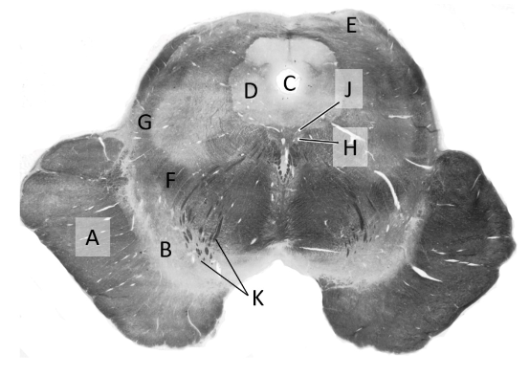

at what level is this?

mid pons

what is a?

cerebellum

what is b?

superior cerebellar peduncle

what is c?

middle cerebellar peduncle

what is d?

trigeminal nerve

what is e?

pyramidal fibres

what is f?

transverse pontine fibres

what is g?

4th ventricle

what is h?

median longitudinal fasciculus (p)

what is j?

medial lemniscus (p)

what is k?

spinothalamic tract (p)